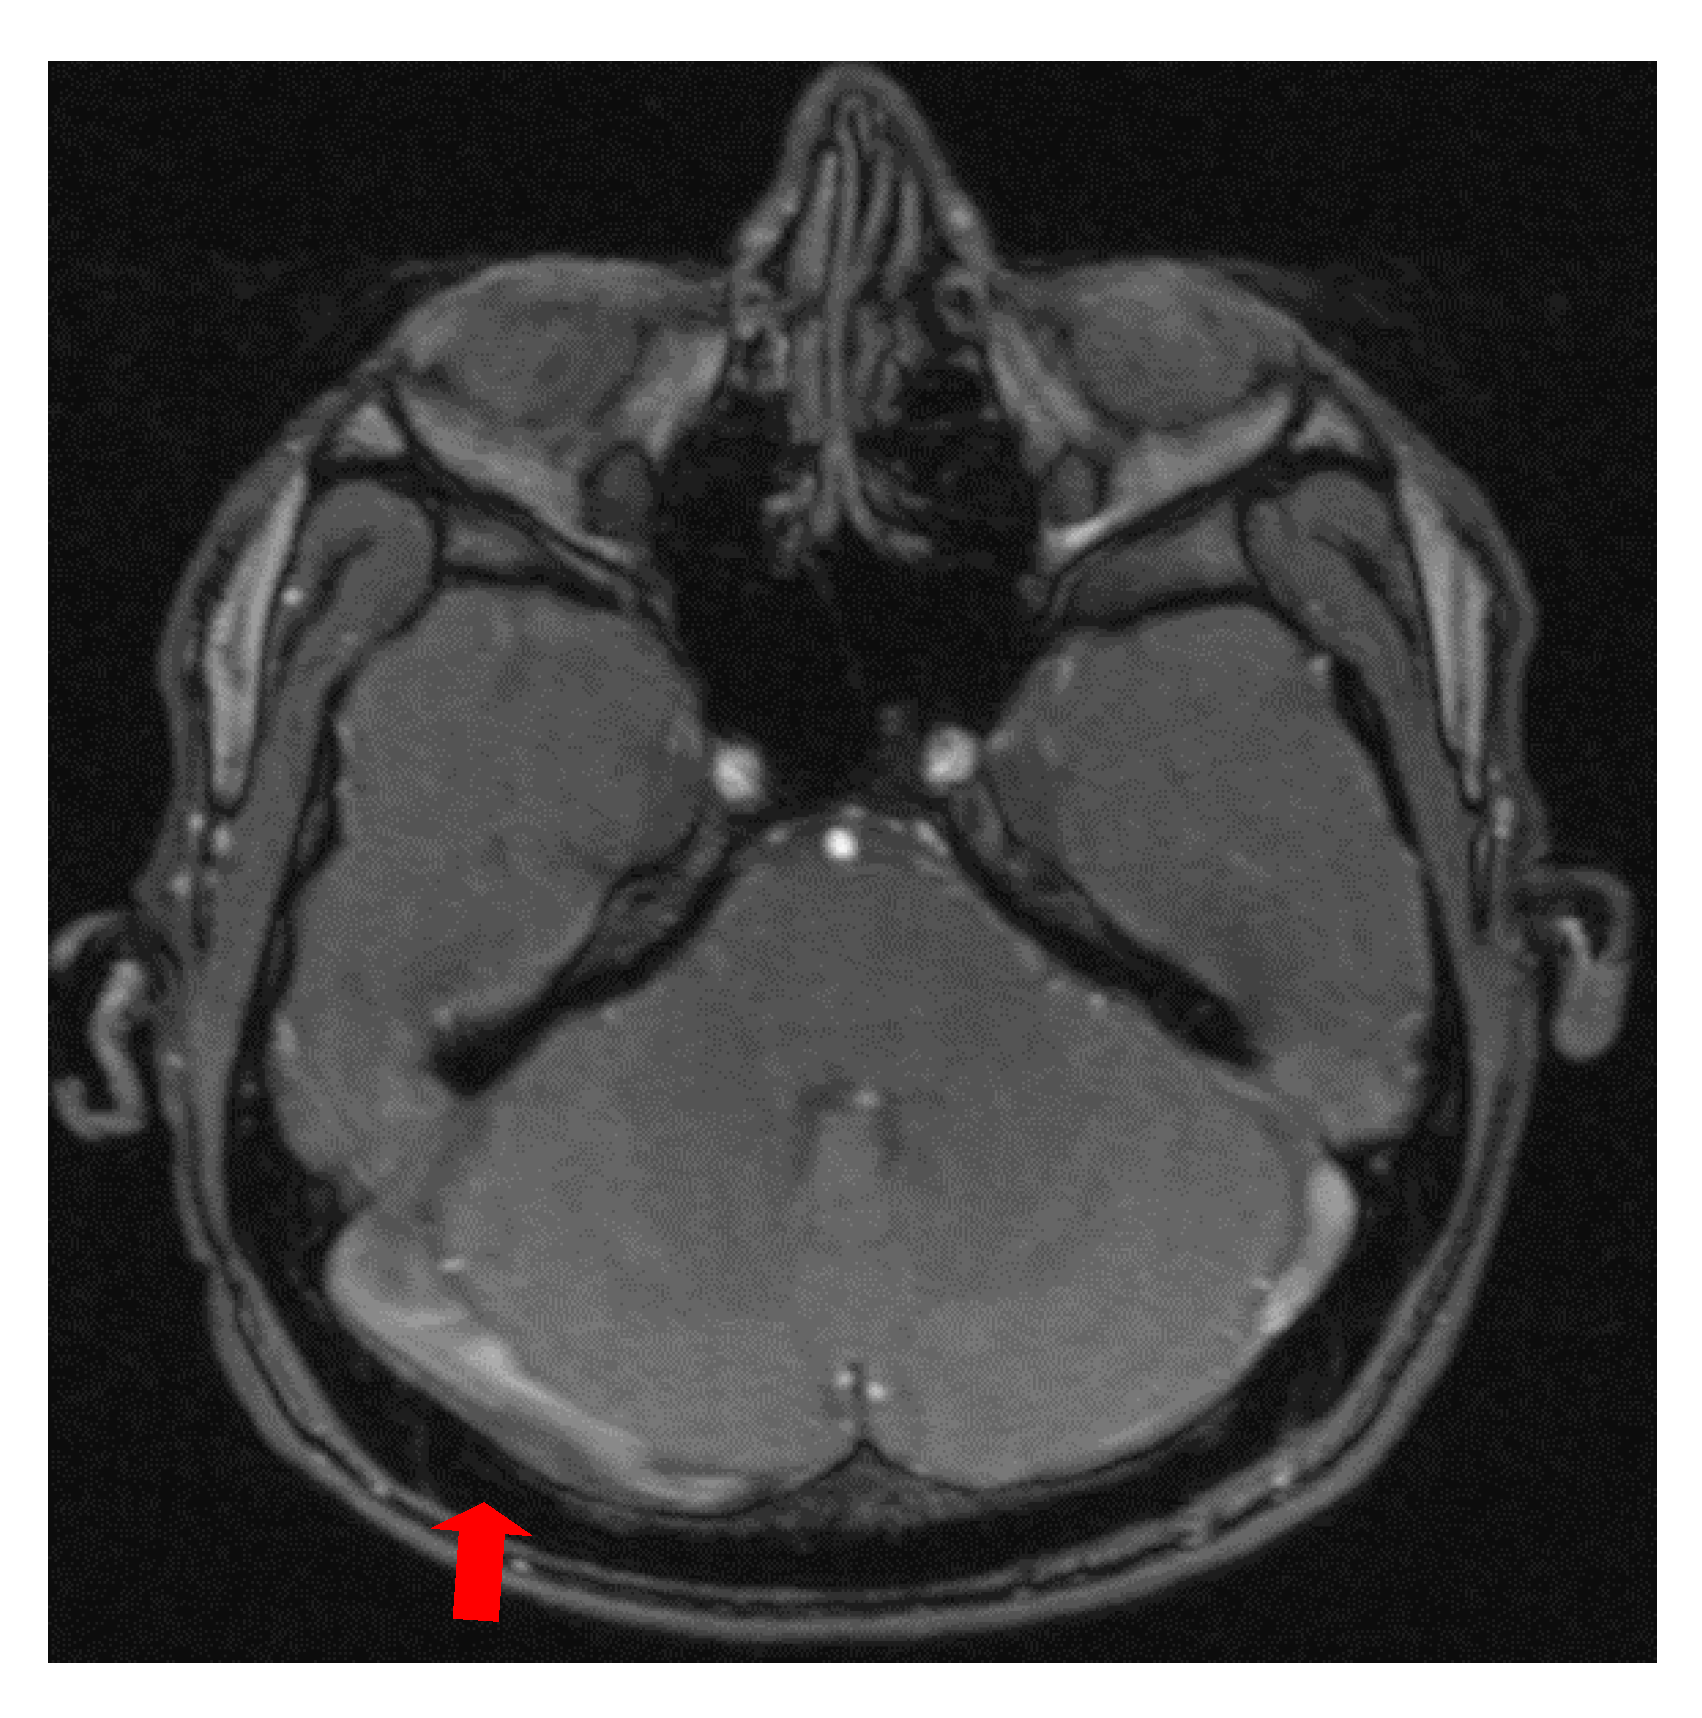

The first case, was a female, 26 years old, with an etiology of left otomastoiditis, hospitalized in superficial coma, with meningeal symptoms and HIC, psychomotor agitation and three generalized seizures. The Grisinger sign was present at local examination of mastoiditis. After a period of six months, at the reevaluation, the same patient did not present any residual symptomatology related to thrombophlebitis. The imagistic features can be seen in Figure 1 and Figure 2.

Figure 1. MR-venography 2D-TOF (2D- time of flight) in the coronal (a) and axial (b) plane noting the absence of the flow in the left lateral sinus (thrombosis of the left LS at the onset).